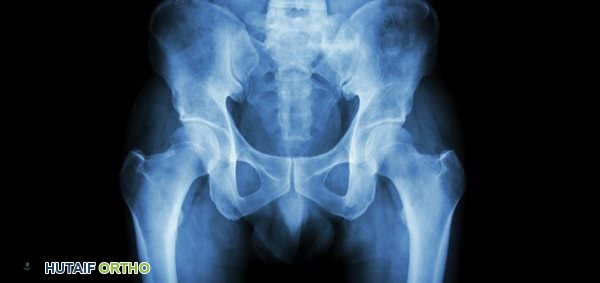

• الأشعة السينية (X-rays):

• هي الفحص الأول والأساسي لتشخيص التهاب مفصل الورك التنكسي. يمكن للأشعة السينية أن تظهر علامات مميزة للخشونة مثل:

• تضيق المسافة المفصلية: يشير إلى تآكل الغضروف.

• تغيرات في العظام: مثل تصلب العظم تحت الغضروف (Subchondral Sclerosis).

• النتوءات العظمية (Osteophytes): وهي نتوءات عظمية صغيرة تتشكل على حواف المفصل.

• الخراجات تحت الغضروفية (Subchondral Cysts): وهي جيوب صغيرة مملوءة بالسوائل تتشكل في العظم تحت الغضروف.

• يتم أخذ صور من زوايا مختلفة لتقييم المفصل بشكل كامل.

صورة بالأشعة السينية لمفصل ورك مصاب بالخشونة